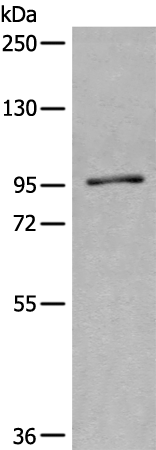

分类: 科研抗体货号: P11230别名: C17orf71应用: WB反应种属: Human, Mouse